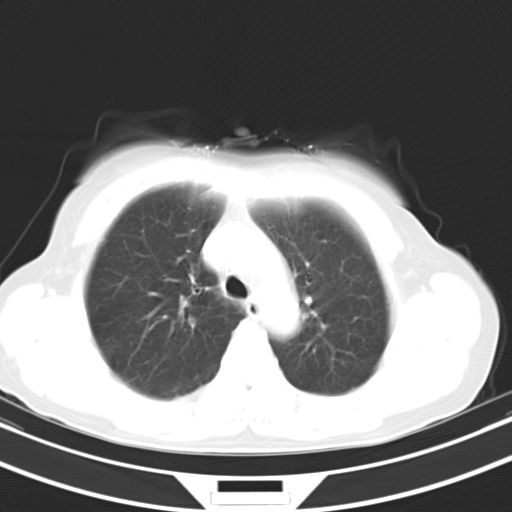

女,47岁,咳嗽胸痛一个星期,我们考虑肺结核,左下肺病灶肿瘤像不像,请高手指点。急。

左上肺舌叶实质性病变,形态呈楔形,内可见支气管气像,中至重度强化,考虑为炎性改变,建议复查

考虑右肺上叶前段及左肺舌叶炎症,建议抗炎治疗后复查除外结核。

左肺舌叶病灶呈扇形分布,其内可见支气管影,胸膜面光滑,不支持肿瘤病变。